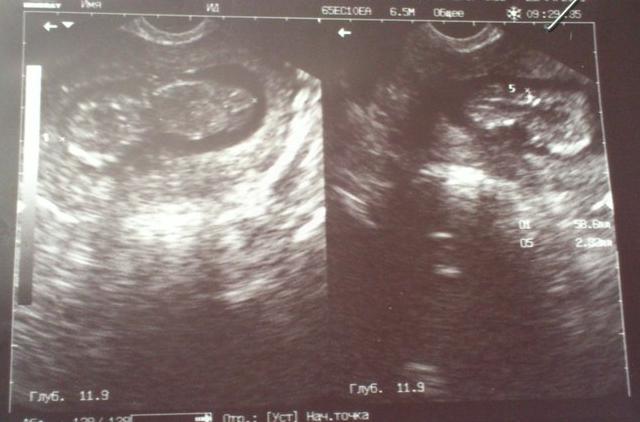

... Я поревела конечно от счастья! Самое главное начали узи делать а карапузька моя - спит! Мне врач говорит счас я его попробую разбудить.... пошевелила датчиком... а малыш, поморщил носик махнул на нас ручкой и повернулся к нам попой))))) Врач мне кусочек шоколадки дает - еш говорит ато ничего не получится. Я сьела и минут через пятнадцать мой ангел проснулся и начал активничать

. Тут уж мы всё и посмотрели.